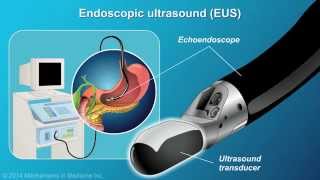

EUS Guided Fine Needle Biopsy of a Pancreatic Mass video

EUS-Guided Fine-Needle Aspiration for the Diagnosis & Staging of Pancreatic Masses

EUS-Guided Fine-Needle Aspiration for the Diagnosis & Staging of Pancreatic Masses Endoscopic Ultrasound with Fine Needle Aspiration Biopsy

Endoscopic Ultrasound with Fine Needle Aspiration Biopsy Understanding EUS-FNA

EUS-Guided Fine-Needle Aspiration for the Diagnosis & Staging of Pancreatic Masses

EUS-Guided Fine-Needle Aspiration for the Diagnosis & Staging of Pancreatic Masses Endoscopic Ultrasound with Fine Needle Aspiration Biopsy

Endoscopic Ultrasound with Fine Needle Aspiration Biopsy Understanding EUS-FNA